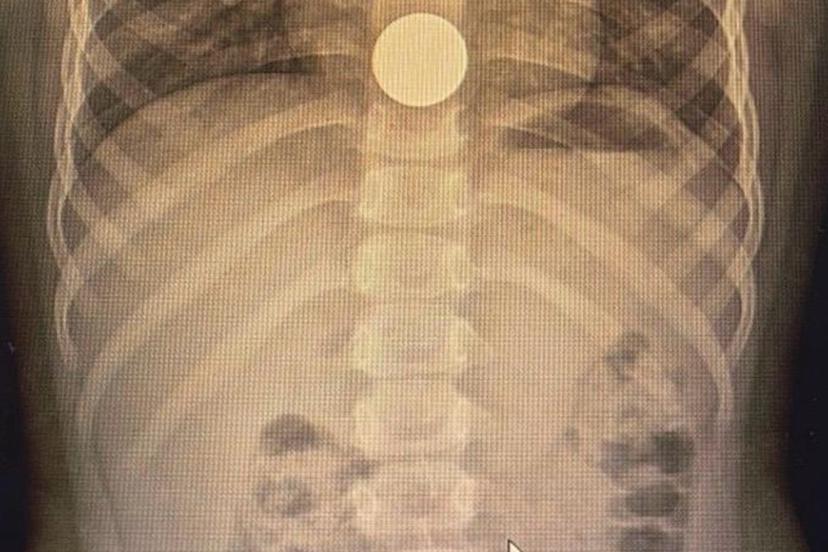

Solunum yollarına yabancı cisim kaçmasının da önemli bir risk olduğuna dikkat çeken Özkaya "Solunum yollarına yabancı cisim kaçması da günlük hayatta sık karşılaşılan ve hayati tehlike oluşturabilen durumlardan biridir. Özellikle üç yaşına kadar olan çocuklara çerez, fındık, fıstık, çekirdek gibi sert gıdaların verilmemesi gerekmektedir. Bu gıdalar solunum yollarına kaçarak ciddi nefes darlığına neden olabilmektedir. Böyle bir durumla karşılaşıldığında, mümkünse Heimlich manevrası uygulanmalı ve 112 Acil Servis eşliğinde en yakın sağlık kuruluşuna başvurulmalıdır. Bu tür vakaların operasyon gerektirebileceğine dikkat çekilerek, özellikle yemek borusunda kalan disk pillerin son derece tehlikeli olduğu vurgulanmaktadır. Disk piller, çocukta belirgin bir şikâyet olmasa bile kısa sürede yemek borusunda yanıklara ve delinmelere yol açabilmekte, hayati risk oluşturabilmektedir. Bu nedenle acil olarak ameliyathane ortamında çıkarılmaları gerekmektedir." şeklinde konuştu.